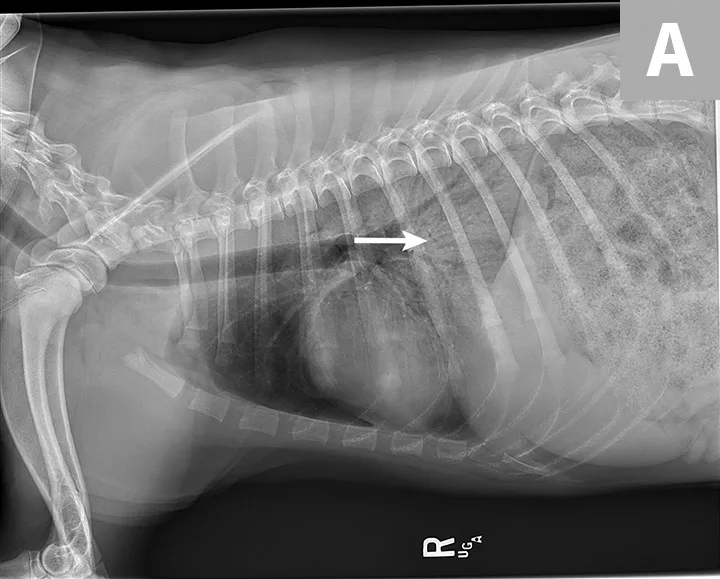

Blood pressure was decreased (85 mm Hg) on Doppler ultrasound. Oxygen saturation was initially 92% but increased to 98% with flow-by oxygen supplementation via mask (4 L/minute). Initial blood work showed mild hyperlactatemia (3.1 mmol/L; reference range, 0-2.5 mmol/L), packed cell volume of 54%, and total solids at 6.8 g/dL. Chest radiography was performed with oxygen supplementation and revealed a moderate to severe caudodorsal interstitial to alveolar lung pattern (Figures 1 and 2).

Radiographs showing caudodorsal alveolar pattern consistent with noncardiogenic pulmonary edema (arrows). Edema is caudodorsal and bilateral. The heart size is normal, and there is no elevation of the airways that would indicate left-sided heart enlargement. Sternal contact of the heart, which might suggest right-sided heart enlargement, is minimal.